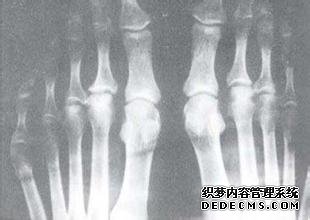

1、近侧指间关节呈梭状肿大,最为常见。其次为掌指、趾、腕、膝、肘、踝、肩和髋关节等。

4、关节受累常从四肢远端的小关节开始,以后再累及其他关节。

5、关节疼痛、僵硬、肿大,呈对称性,周围皮肤温热、潮红,当自动或被动运动时都会引起疼痛。